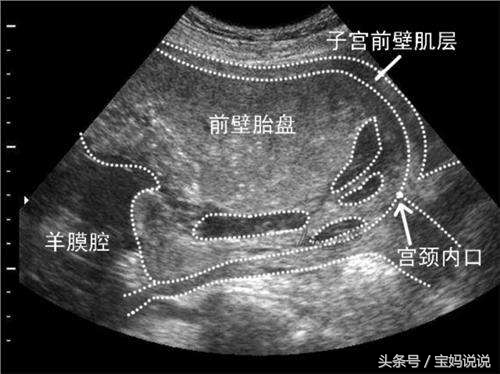

2:前置胎盘

如果在孕中期发现这种褐色分泌物,那大部分可能就是因为前置胎盘了。孕妈都知道正常的胎盘是附着于孕妈子宫的后壁、前壁和侧壁。如果孕28周后胎盘附着于子宫后下段,就属于前置胎盘了,这种情况一般能通过B超检查出来

需要提醒的是:如果你在产检的报告单上看到“胎盘离宫颈口有_毫米”这句话,就提示是否有前置胎盘的危险了。